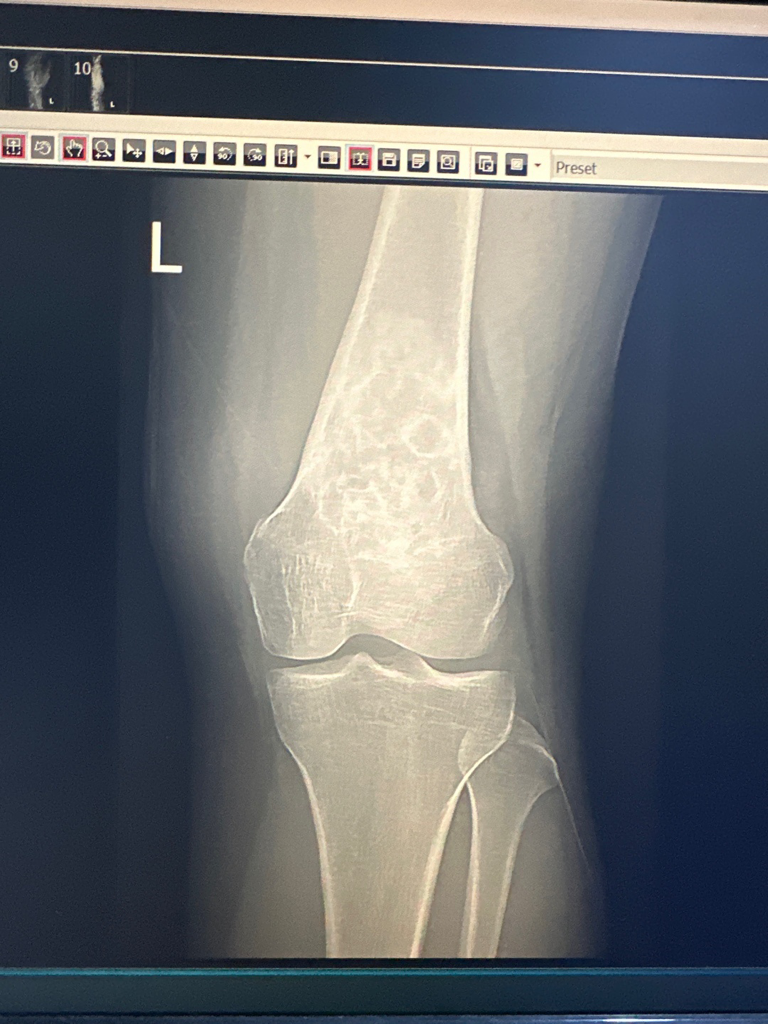

전공이 아니라 말씀드리기가 조심스럽지만 왼쪽 무릎 위쪽의 대퇴골에 덩이로 추정되는 것이 보이고 있어 추가검사를 요하는 것 같습니다. 골종양을 확인해야만 하는 상황이라 보입니다만 강력히 권한 정도가 아니라면 악성을 의심하시는 것 같지는 않습니다.